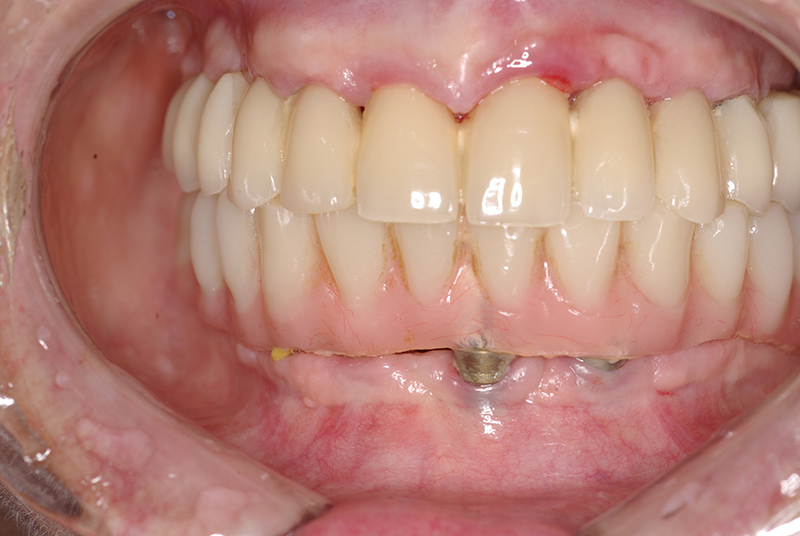

- Planejamento Digital: Com o auxílio de tecnologias como tomografias e softwares 3D, a posição dos implantes é planejada com precisão.

- Cirurgia de Instalação dos Implantes: Os implantes são fixados no osso maxilar ou mandibular, proporcionando uma base sólida para a prótese.

- Fixação da Prótese: Em até 72 horas após a cirurgia, a prótese provisória é instalada, permitindo que o paciente recupere a funcionalidade e a estética imediatamente.